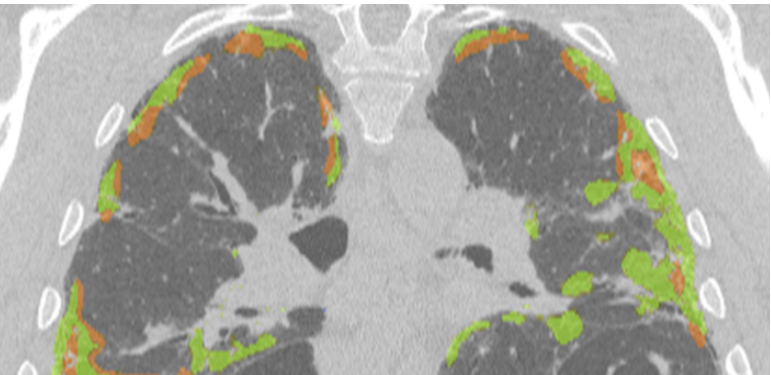

Our subspecialist chest radiology experts use cutting-edge Artificial Intelligence (AI) software to interpret your low-dose CT chest scan and provide a detailed lung health assessment. Our service is designed both for patients with symptoms as well as those with identified risk factors for lung disease, including lung cancer. H&L chest experts provide a detailed lung health report within 2 days.

A low dose CT scan with cutting edge AI enables detailed measurement of emphysema and the early diagnosis of lung fibrosis, including long COVID lung scarring.